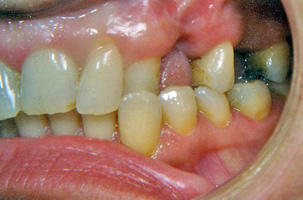

Προβλήματα λόγω της κακής θέσης των γνάθων μεταξύ τους μπορούν με την κατάλληλη ορθοδοντική μετακίνηση των δοντιών να καμουφλαριστούν και να επιτευχτεί μια αποδεκτή σύγκλειση παρά την υπάρχουσα σκελετική ανωμαλία. Παρόλα αυτά, όταν οι διαφορές μεγέθους ή/και οι σχετικές σχέσεις των γνάθων μεταξύ τους είναι έντονες, δεν είναι δυνατή η διόρθωση αποκλειστικά με την ορθοδοντική θεραπεία. Σ’ αυτες τις περιπτώσεις η ορθογναθική χειρουργική είναι απαραίτητη παράλληλα με την ορθοδοντική θεραπεία. Σε μεικτά προβλήματα όπου εμπλέκονται τόσο τα δόντια όσο και ο σκελετός, δεν είναι δυνατόν η ορθογναθική χειρουργική να αντικαταστήσει την ορθοδοντική, αλλά ούτε και η ορθοδοντική μόνη της μπορεί να διευθετήσει σωστά το συνολικό πρόβλημα. Για την αντιμετώπιση μεικτών προβλημάτων υπάρχει συγκεκριμένο πρωτόκολλο συνεργασίας. Ο ορθοδοντικός και ο γναθοχειρουργός μετά από κοινό έλεγχο του ασθενούς παίρνουν τις διαγνωστικές καταγραφές (εκμαγεία, ακτινογραφίες, φωτογραφίες) και αφού μελετήσουν το πρόβλημα, καταστρώνουν το σχέδιο θεραπείας και ορίζουν τις αρμοδιότητες των δυο ειδικοτήτων. Η θεραπεία κατά κανόνα έχει τρεις φάσεις:

1. Προχειρουργική ορθοδοντική:

Ο ορθοδοντικός καλείται να φέρει τα δόντια της κάθε γνάθου σε θέσεις τέτοιες ώστε μετά το χειρουργείο που θα ακολουθήσει, να επιτευχτεί μια ισορροπημένη σύγκλειση. Η διάρκεια της προχειρουργικής ορθοδοντικής θεραπείας είναι δυνατόν να ποικίλλει κατά περίπτωση από 12 έως 24 μήνες.